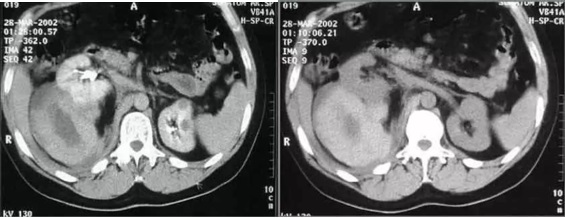

La Categoría I define la lesión como densidad agua (0-20 UH), sin septos o calcificaciones, ausencia de polos sólidos y sin realce a la administración de medio de contraste yodado IV.(19, 20) Su clasificación sería de quiste simple benigno y no requeriría ningún tipo de evaluación posterior. Son lesiones asintomáticas que rara vez requieren tratamiento. No es necesario realizar controles posteriores (Anexos 3 y 4).

La Categoría II define una lesión con septos finos lisos (< 1mm), calcificaciones lineales continuas o discontinuas o lesiones densas homogéneas en la pared o tabique pero que no experimentan realce a la administración de medios de contraste yodado IV en TC o paramagnéticos en RMI. Su clasificación es de lesión benigna (proteáceos, hemorrágicos, infecciosos).(19, 20) Estos quistes son hiperdensos (40-90 UH < 3cm), mínimamente complicados y no precisan cirugía, deben ser controlados (Anexos 5 y 6).